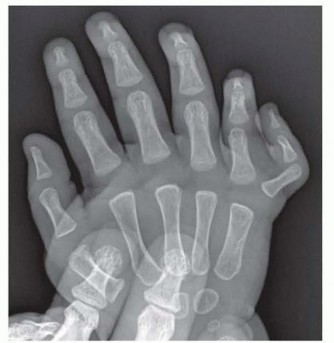

In cases of digit duplication, one may observe duplication in some or all of the elements of the finger (bone, nail, joints, and tendon). The duplicate finger may be well formed and near normal in appearance or underdeveloped and rudimentary in appearance.Wassel published a classification of thumb duplication based on the work of Adrian Flatt, MD (Table 1). Postaxial polydactyly classificationType A: well-formed duplicate small finger with bone or tendon attachments (FIG 1) Type B: small pediculated nubbin

FIG 1 • Type A postaxial polydactyly.